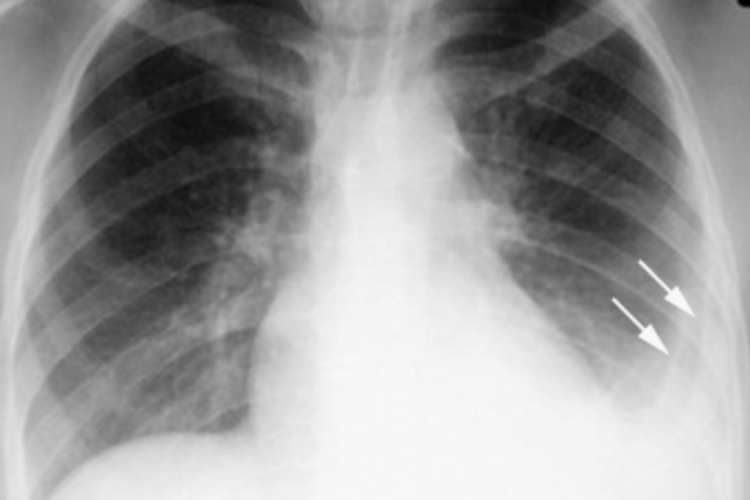

典型表现呈“哑铃”状,邻近胸膜处的肺内原发病灶,多位于中上肺野,呈圆形、类圆形或局限性斑片影。若有淋巴管炎可出现自原发性病灶向肺门走行的不规则条索状影。若有肺门、纵隔淋巴结增大,可表现为肺门影增大或纵隔淋巴结增大,并突向肺野。